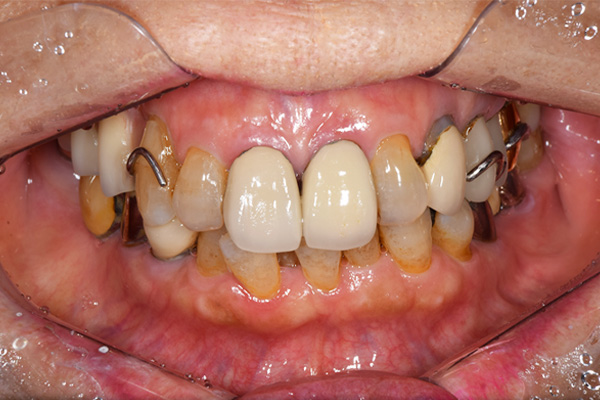

ケース5(金属使用 部分床義歯)

入れ歯をなくしてしまったので、あたらしく作りたい患者様です。

お口に入っている状態です。嘔吐反射が強かったため、うわあごの部分をくり抜いて作っています。

そのためにはしっかり歯に維持力をかける事、歯茎の部分に圧をかけるため、金属をつかって入れ歯を作成しました。

年齢 80代・女性

主訴 入れ歯をなくしたのであたらしくつくりたい。

治療期間 1ヶ月

治療費 義歯:330,000円(税込)

治療方針 以前作った入れ歯は気に入っていたが無くしてしまったとのことで、作り直しました。

上には残っている歯がありますが、入れ歯がない状態が続くと、歯へのダメージが強いことが考えられましたので、急ピッチで作っていくことにしました。

治療内容 入れ歯をつくるための前処置はとくに必要なかったため、すぐに入れ歯を作成していきます。

嘔吐反射が強く、普通の上顎の入れ歯を入れた時の違和感が強いため、口蓋部をくり抜いてつくっていきました。

そのため、歯や粘膜に維持負担を強くかけるため、金属を使用していくことにしました。

患者さんのお話をきいていると、前の入れ歯もそういう入れ歯をつくっていたとのことでした。

特記事項 入れ歯は完成してからがスタートです。入れ歯が歯ぐきにこすれて痛みが出る事が多いです。

今回の様な入れ歯ではそういう事が必ずと言っていいほどでます。

そのため、しっかり痛みをとるために入れ歯を調整して、患者さんに合わせた入れ歯にカスタマイズして完成になります。